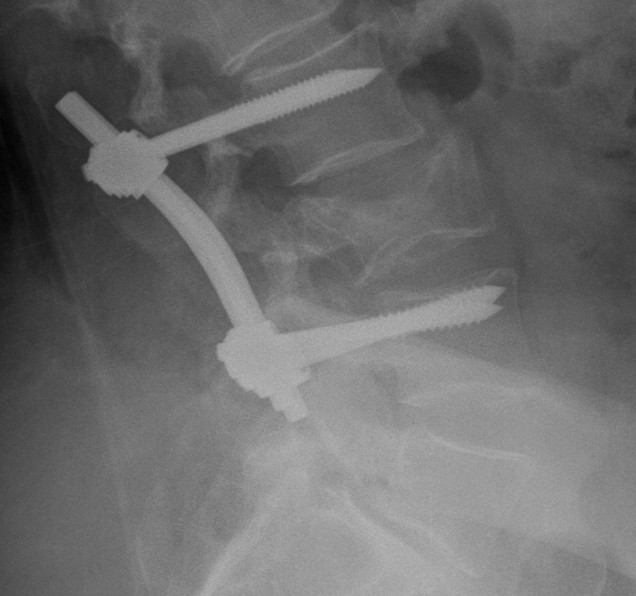

Posterior instrumentation

Indication

- < 7 gaines criteria

- no neurology

Technique

- ligamentotaxis clears canal / PLL acts as bowstring

- pedicle screws lumbar, avoided in thoracic

- use transverse process and pedicle hooks in thoracic

- bone graft inserted via pedicles

- need to do before 5 days post injury